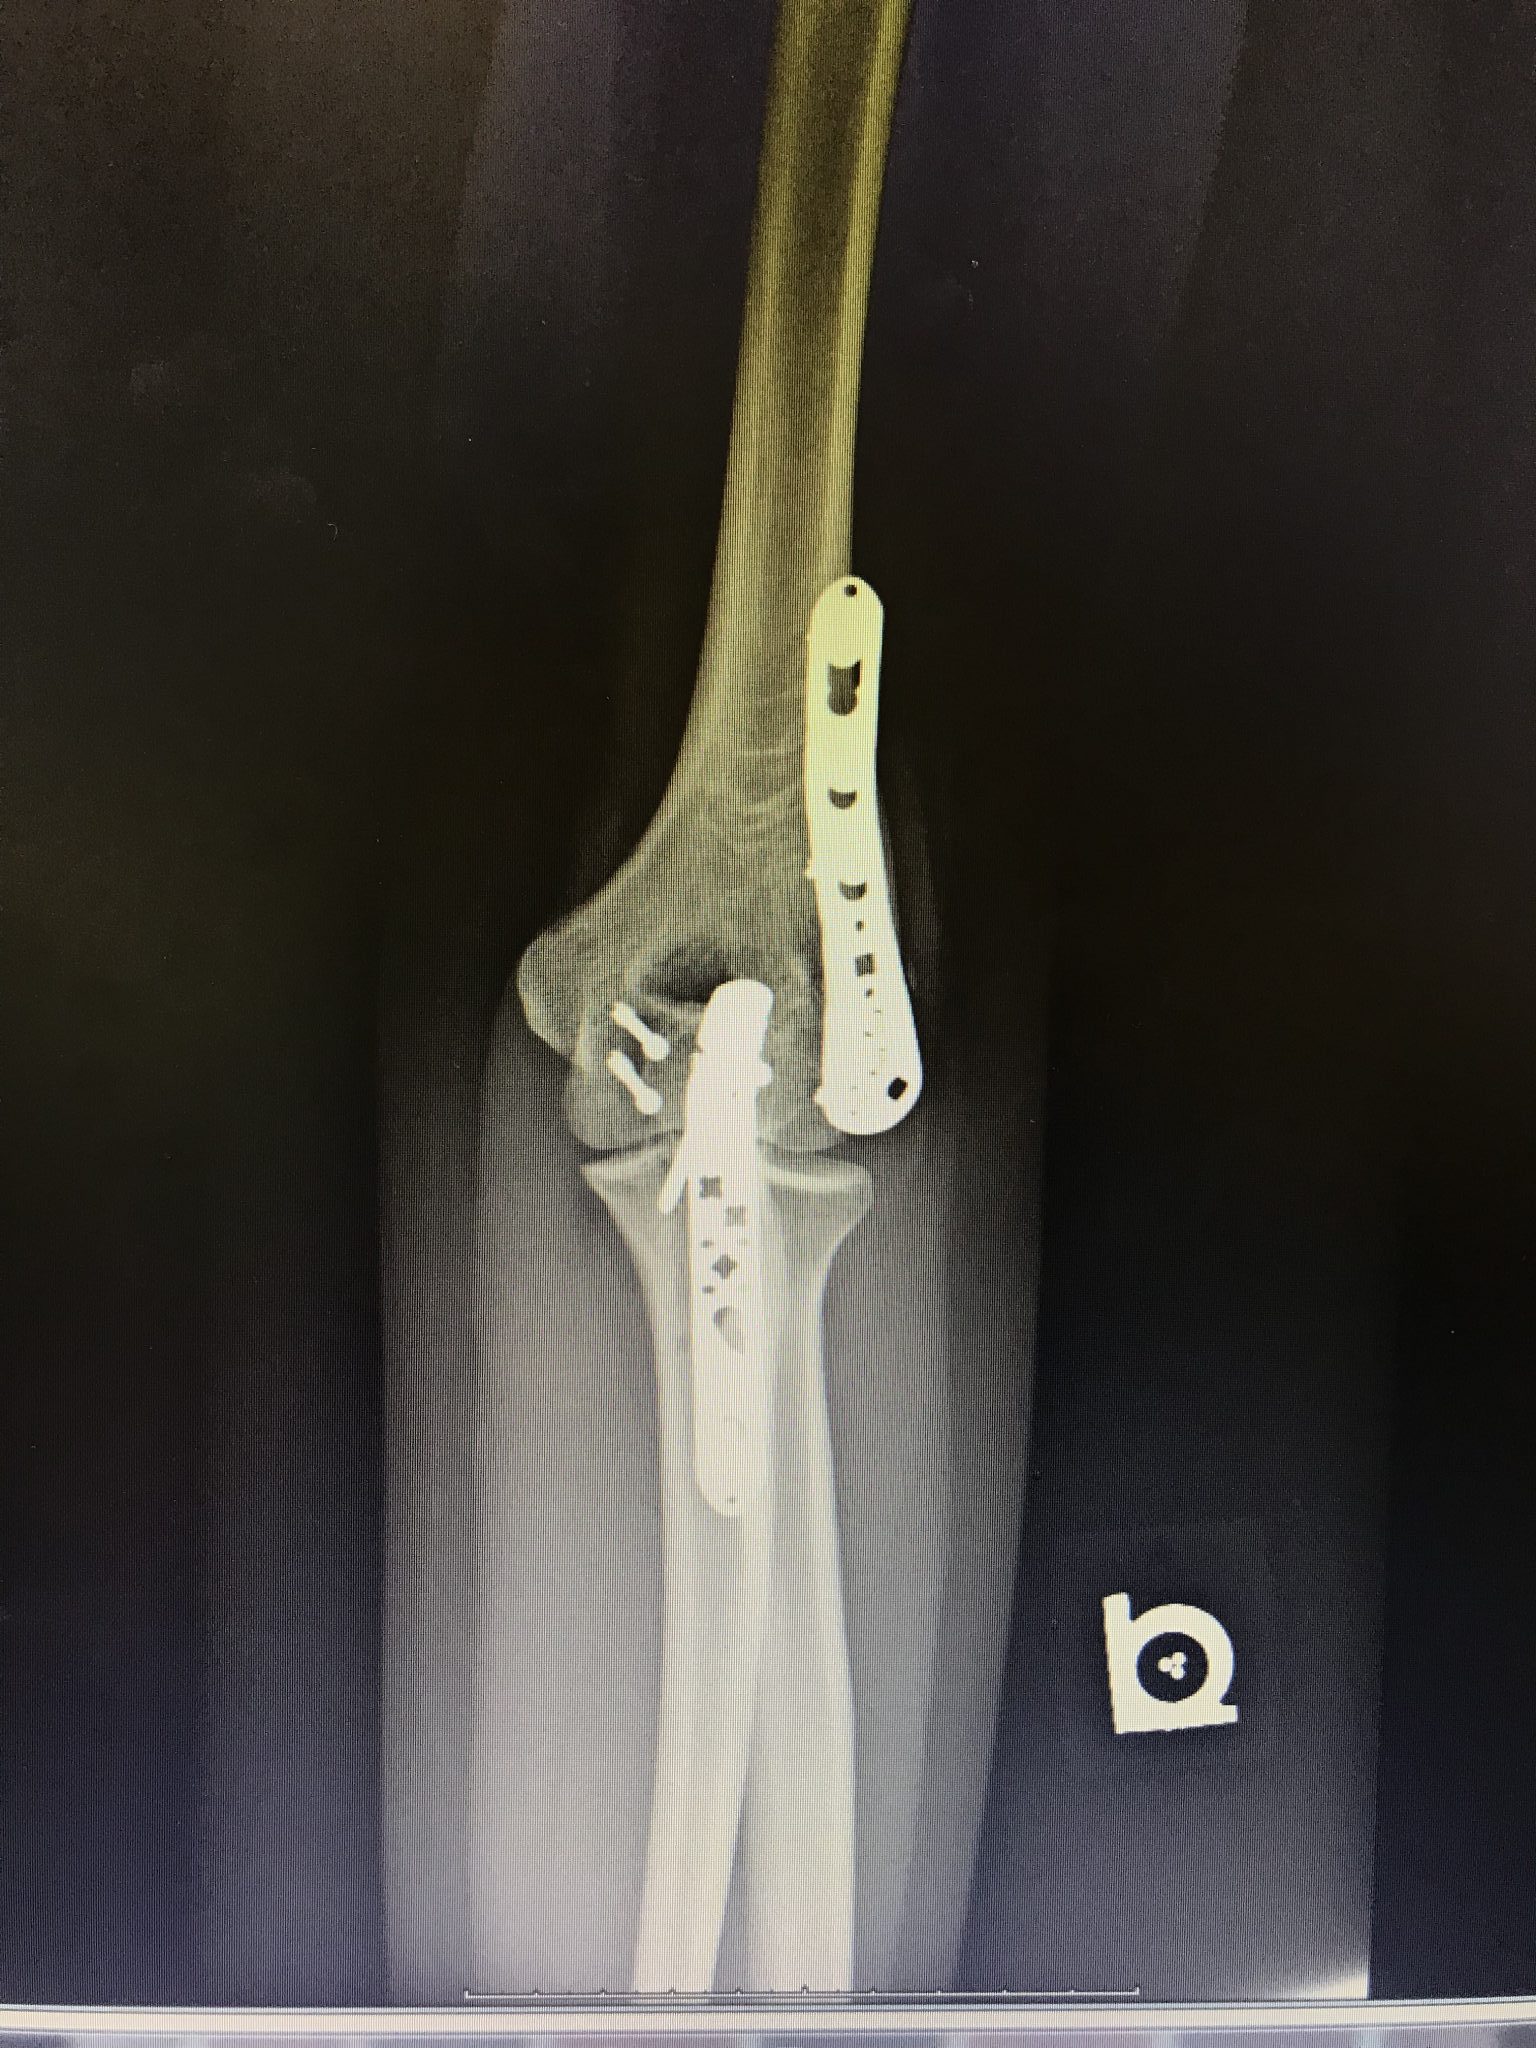

BGO's latest Champion patient comes from London, KY - Ms. Sydney Parker. Sydney is an animal lover, and was injured after a fall from her horse in October of 2018. She fractured and dislocated her elbow, which unfortunately led to surgery in October of 2018 - a complicated procedure that required an open reduction internal fixation as well as an ulnar nerve decompression and transposition. Sydney had fractured her trochlea, lateral condyle of her elbow, as well as her olecranon.

Dr. Donegan, BGO's shoulder and elbow specialist, said this about Sydney and her injury: "Sydney's fracture was very severe and involved the joint surface of the elbow. As a result, we needed to align the pieces anatomically to decrease her risk of arthritis in the long term and increase her range of motion and function. From the instant I met with Sydney and her family, you could tell she was going to keep a positive attitude and work to get better. She has an optimism about her that inspires others around her!"

"Dr. Donegan and the staff at Bluegrass Orthopaedics were amazing throughout my journey with them⦠Dr. Donegan said it was an abnormal and very severe (fracture), but assured me that he would be able to fix it. With a couple plates, several screws, and a few weeks of recovery, I was back on my horse with an intact elbow and a really awesome scar! I honestly couldn't thank him enough for how well he took care of me and how wonderful the staff treated me during recovery. They were a true blessing!"